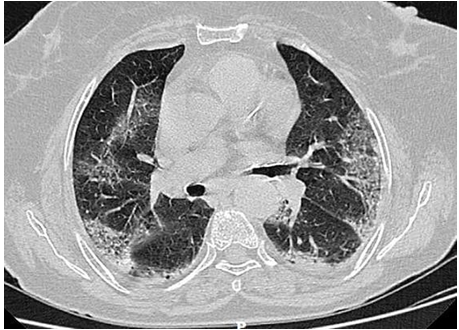

Fig. 3: Ground glass opacity (GGO) with septal thickening

Present study out of 107 cases 106 cases had abnormal HRCT findings out of which 99(92.5%) had bilateral abnormality and 7(6.5%) had unilateral abnormality and 7 had normal HRCT finding. Similar finding observed in [9] showed out of total of 175 chest CT scans were scored in this study. A total of 140 (80%) chest CT scans demonstrated bilateral infiltrates, and 31 (18%) chest CT scans showed unilateral infiltrates, whereas 4 (2%) chest CT scans had no abnormal findings. In our study, according to HRCT findings, GGO was seen in 70(65.4%) cases, consolidation in 34(31.8%), atelectatic band in 1(0.9%), crazy paving in 5(4.7%) cases, reticulation in 11(10.3%) cases, Peripheral hyperdensity in 9(8.4%), mediastinal LN and lymphadenopathy 2(1.9%) cases respectively, 1(0.9%) case with COPD, ground glass haziness, emphysematous changes, mild Fibrosis and septal thickening respectively. Similar findings observed in Sudhir Bhandari et al.119. (2020) showed that in an early phase of disease (10 d), among radiologically positive patients (8 out of 15) 12.50% patients had GGO, 75.00% patients had both GGO and consolidation, while remaining 12.50% patients had only consolidation in imaging of HRCT chest.